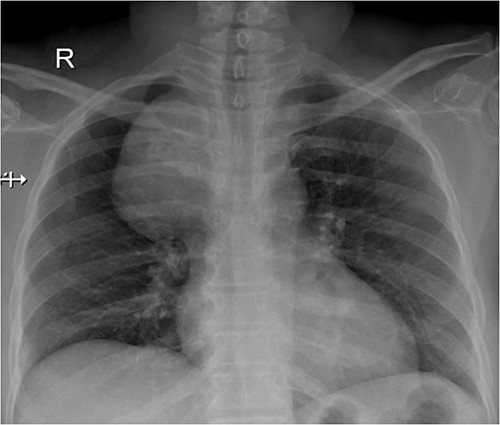

A 57-year-old female came with chest discomfort and cough since 1 month. The chest X-ray (Fig. 1) showed mass in the superior mediastinum. CECT thorax (Fig. 2) revealed the soft tissue density 7 cm × 7 cm (Fig. 3) in superior mediastinum abutting subclavian artery, azygous vein, anteriorly displacing superior venacava, anteromedially abutting arch of aorta, posteromedially compressing trachea and abutting right main bronchus. A 4.9 cm × 5 cm mass in the left side superior mediatinum was seen abutting internal jugular vein and brachiocephalic artery. USG showed the presence of normal thyroid in the neck. CT guided biopsy from the right mass showed ectopic thyroid tissue (ETT)-colloid goiter. Due to close proximity with major vessels sternotomy done. Mass in the left side 5 cm × 5 cm (Fig. 4) in the superior mediastinum was identified, on dissecting superiorly, which was free from the thyroid in the neck and abutting the IJV, brachiocephalic artery and left innominate vein that were separated with meticulous dissection.

CECT scan showing the right side mass displacing superior nn(SVC).